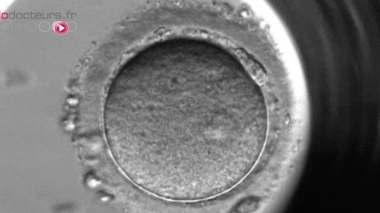

"Cellfie" : la fécondation in vitro dans l’album photo

Un embryoscope (image d'illustration)